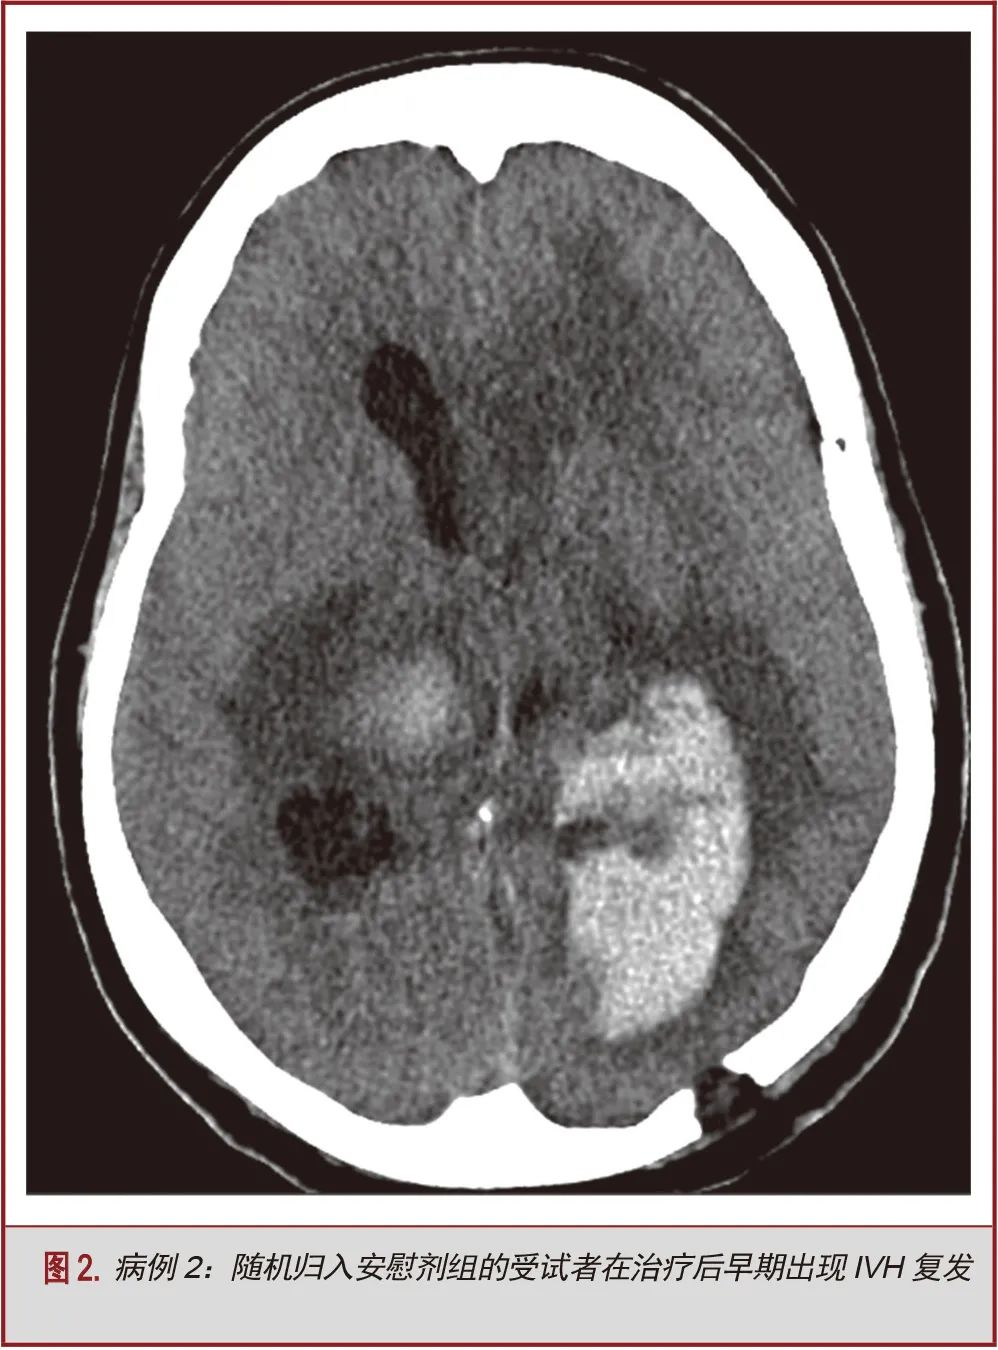

5名受试者在给药72小时后和前30天出现症状性再出血。该组中仅2名受试者在给药期间接受阿替普酶治疗(40%)。该组中出现的症状性再出血事件为:导管相关性出血(n=2,40%),IVH扩张(n=2,40%)和新发脑叶ICH(n=1,20%)。在出血时,2名受试者(40%)已接受预防性抗血栓治疗。1例(20%)接受了治疗量的抗凝治疗,属于方案偏离。另一例严重的方案偏离行为是:为INR升高的患者进行阿替普酶治疗;尽管是在出血前5天进行这一操作,但它仍可能是导致出血的原因(表2)。患者女,66岁,非洲裔,诊断丘脑ICH合并IVH,行双侧EVD,随机归入安慰剂组。在进行12次生理盐水推注后到达治疗终点。在最后一组盐水推注后的23天,病人再次出现IVH,予置入EVD治疗脑积水,同时继续预防性抗血栓治疗。出血可能是由于重复或多次置管及预防性抗凝治疗(图2)。